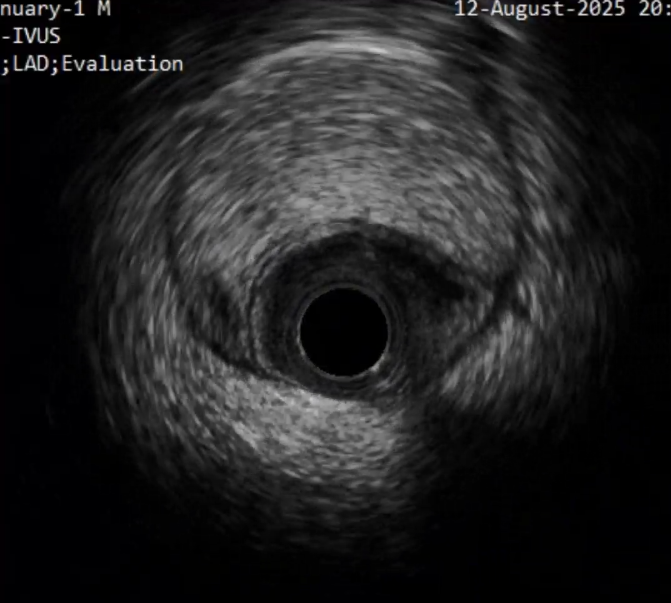

首先进行正向准备,对角支回撤IVUS明确CTO入口,Pilot200导丝进入

IVUS证实导丝进入CTO入口正确